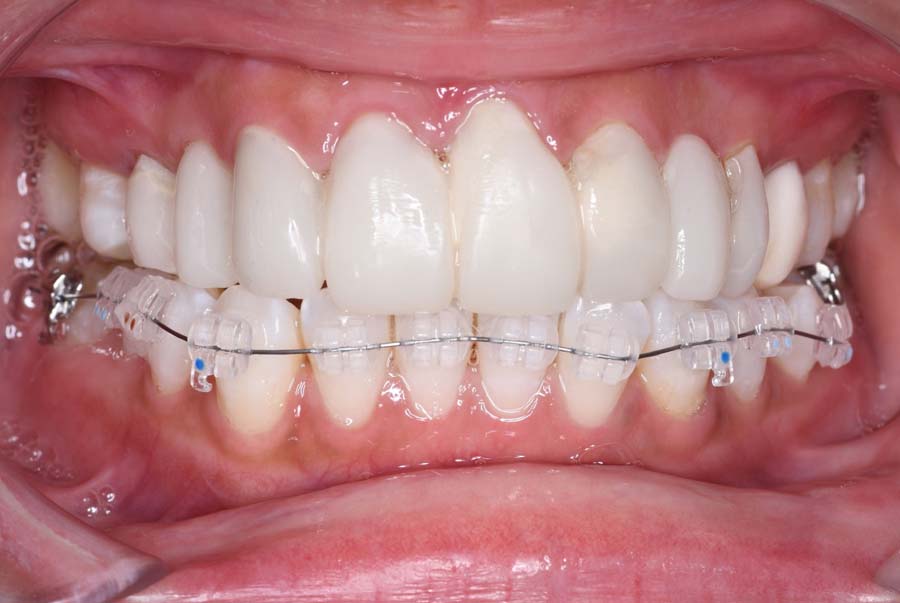

⑤2024年5月 上顎前歯部8本へ仮歯(TEK)

を装着

バイトアップ後

2024年 10月 下顎MTM開始